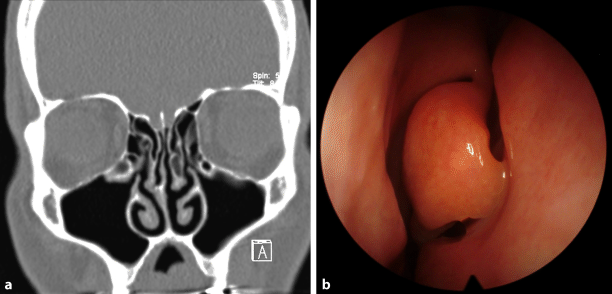

Skelettale Veränderungen 3.10: Concha bullosa - MT-Dialog

Concha Bullosa • Medizinisches Portal de.MEDtube.net

Behandlung von Concha bullosa (luftgefüllte Nasenmuschel) - Op.Dr. Abdülkadir Göksel - Nasenästhetik